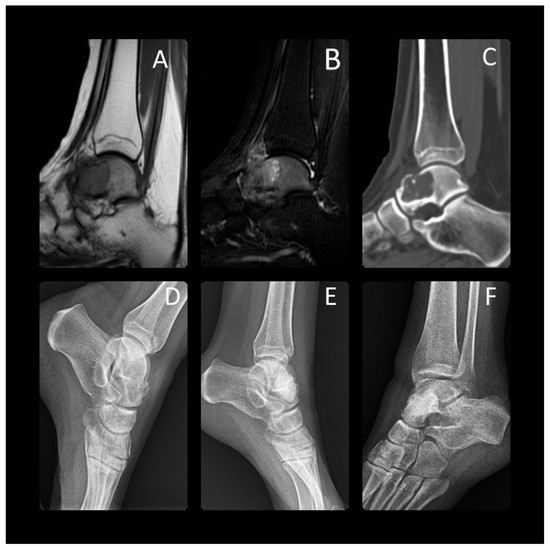

Figure 2. At the age of 14 years, this patient presented with chondroblastoma of the proximal tibia epiphysis, which is clearly shown on MRI (A), CT (B) and X-ray (C). The bone lesion was located in the proximal epiphysis of the tibia, with intralesional calcifications, an irregular sclerotic rim, and a thinned cortex. This active bone lesion crossed the physis. T2-weighted (A) coronal magnetic resonance images show the marrow edema of the epiphysis and metaphysis surrounding the chondroblastoma. This was treated with aggressive curettage and filled with synthetic bone graft. The final radiographs were taken 1 year (D), 3 years (E), and 7 years (F) after surgery. The anteroposterior (F) radiograph shows the lesion has completely healed and there does not appear to be any damage to the growth plate.